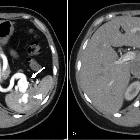

Endovascular

management of incidentally discovered splenic arteriovenous fistula resulting from ruptured splenic aneurysm: Case report and review of the literature: Fig. 1. CT of the abdomen in arterial phase demonstrates fusiform arterial aneurysm (arrow) at the splenic hilum with intrasplenic tangle of vessels (arrowhead) (A). Figure (B) demonstrates dilated splenic vein (arrow).